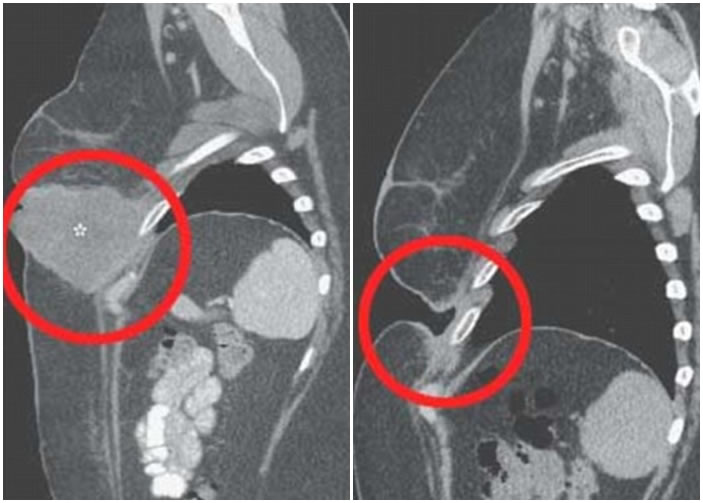

女患者经新混合疗法后,左胸下的巨型肿瘤 (左图)神奇消失,皮肤留下一个大洞(右图)。

报告指,女患者两年半前黑色素瘤复发,5个月前发现左胸底下长出巨瘤,更穿过皮肤凸出。医生向她处方一剂ipilimumab配新药nivolumab的混合药物,她三周后覆诊时发现已无癌细胞。在其馀接受此新疗法的皮肤癌患者中,约6成人肿瘤缩小,惟副作用比服用传统药物严重。